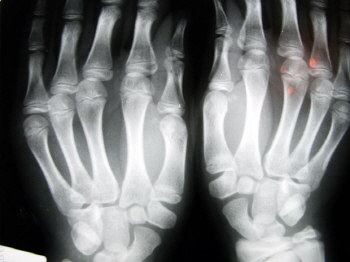

¹æ¾Æ¼è ¼öÁö

¼Õ°¡¶ôÀ» ±¸ºÎ¸®°Å³ª Æî ¶§, ¹æ¾Æ¼è¸¦ ´ç±æ ¶§Ã³·³ ÇÑ ¼Õ°¡¶ôÀÌ ¿ÏÀüÈ÷ ±¸ºÎ·¯ÁöÁöµµ ÆìÁöÁöµµ ¾Ê´Â ¾û°ÅÁÖÃãÇÑ »óŰ¡ µÅ ºÙ¿©Áø À̸§ÀÌ´Ù. ¸¸ÀÏ ¾î¶² ¼Õ°¡¶ôÀÌ ´Ù¸¥ ¼Õ°¡¶ôµé º¸´Ù ´Ê°Ô ÆìÁö°í ¼Õ°¡¶ô ³¡¸¶µð°¡ Àú¸®°í ¾ÆÇÁ¸é ¹æ¾Æ¼è¼Õ°¡¶ôÀ» ÀǽÉÇØºÁ¾ß ÇÑ´Ù. °£È¤ ¼Õ°¡¶ôÀ» Æî¶§ ¶Ò ÇÏ´Â ¼Ò¸®°¡ ³ª±âµµ ÇÑ´Ù.

»óŰ¡ ´õ ÁøÀüµÇ¸é ¼Õ°¡¶ôÀ» Æì°Å³ª ±¸ºÎ¸± ¶§ ¿ë¼ööó·³ ¿ø»óÅ·ΠµÇµ¹¾Æ¿À´Â Áõ»óÀÌ ³ªÅ¸³­´Ù. ¹æ¾Æ¼è¼öÁö°¡ µÇ´Â ¿øÀÎÀº ¼Õ¸ñ°ú ¼Õ°¡¶ôÀ» ÀÕ´Â ÈûÁÙÀÌ ¼Õ»óµÊÀ¸·Î½á ºñÁ¤»óÀûÀ¸·Î ºÎÇ®¾î ¿Ã¶ó ±× ÈûÁÙÀ» °íÁ¤ÇØÁÖ´Â °í¸® °°Àº ±¸Á¶¿¡ ³¢¾î¹ö¸° °ÍÀÌ´Ù. ÀÚ¿¬È÷ Æì°í ±¸ºÎ¸®´Â ¿òÁ÷ÀÓÀÌ ¸¶À½´ë·Î µÇÁö ¾Ê°í ºÎÀÚ¿¬½º·¯¿öÁø´Ù. ¼Õ°¡¶ôÀ̳ª ¼ÕÀ» ¸¹ÀÌ ¾²´Â ÁÖ¹æÀåÀ̳ª ÁÖºÎ, °ñÇÁ³ª Å״Ͻº¸¦ Áñ±â´Â »ç¶÷, È£¹Ì³ª ¸ÁÄ¡·Î ÀÏÇÏ´Â »ç¶÷µéÀÌ Àß °É¸°´Ù.

½Å ±ºÀÌ ¾Î°í ÀÖ´Â ¹æ¾Æ¼è ¼öÁö´Â ´Ù¸¥¸»·Î ¹æ¾Æ¼è¼Õ°¡¶ôÀ̶ó°íµµ ÇÑ´Ù. ÀÌó·³ ¼Õ°¡¶ô, ¼Õ¸ñ, ¹ß°¡¶ô, ¹ß¸ñ µî ¼¶¼¼ÇÑ µ¿ÀÛÀ» °¡´ÉÄÉ ÇÏ´Â ÀÛÀº °üÀýÀº Áö³ªÄ¡°Ô ¸¹ÀÌ »ç¿ëÇϸé Å»ÀÌ ³ª°Ô µÅ ÀÖ´Ù. ±×·¡¼­ ƯÁ¤ °üÀýÀ» ¹Ýº¹ÀûÀ¸·Î ¿òÁ÷¿©¾ß ÇÏ´Â Á÷¾÷ÀÎÀ̳ª °¡Á¤ÁÖºÎ, ¿îµ¿ ¼±¼öµé¿¡°Ô ¸¹ÀÌ ¹ßº´ÇÑ´Ù.